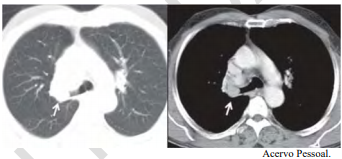

Uma paciente de 47 anos de idade, não tabagista, apresenta episódio de tosse e hemoptise. A tomografia computadorizada de tórax, realizada para investigação, evidenciou um nódulo pulmonar, com densidade de partes moles, de 2,1 cm, com obstrução do brônquio lobar superior direito, demonstrada nas imagens a seguir. Não há linfonodos mediastinais aumentados. A fibrobroncoscopia para investigação evidenciou uma lesão sólida em brônquio lobar superior direito, com obstrução total do brônquio, e aspecto em dedo de luva. As tomografias computadorizadas de abdome e de crânio não identificaram lesões metastáticas a distância. A biópsia endobrônquica demonstrou ser um carcinoide típico.

Trata-se de um estadiamento clínico IA3: T1cN0M0.